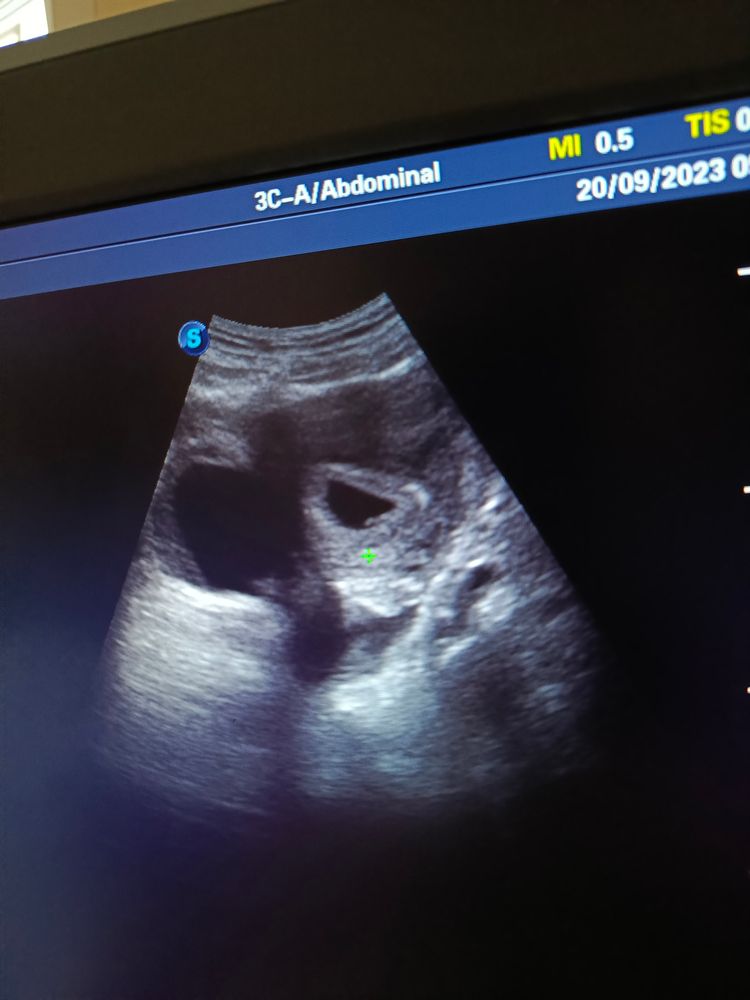

Последние мес 9 августа, тесты положительные все, мес нет с 5 сентября, ходила в женскую поставили 5-6 недель, записали на узи и на 28 на повторный приём, на узи смотрели внутренним датчиком, ничего не увидели, сходила в платную на узи, всё есть, развивается, в шоке как там внутренним ничего не видно...